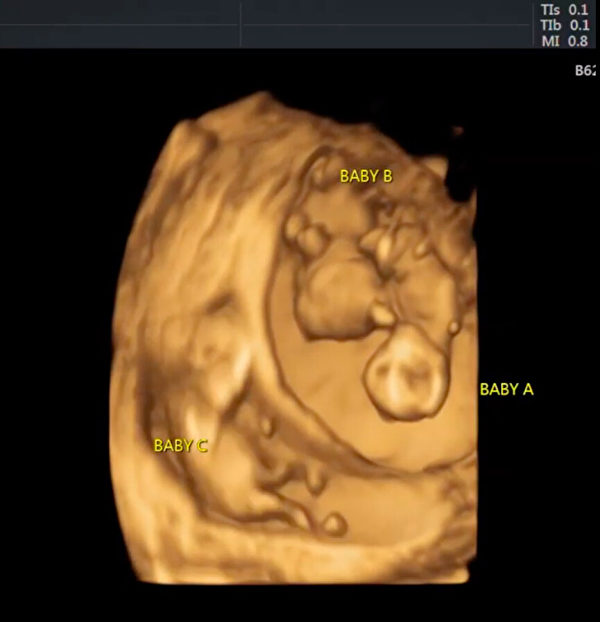

这种现象在医学上又称为异期复孕(superfetation),即妇女在怀孕后继续排卵时,就会发生这种现象。米歇尔的情况是,婴儿A和B是双胞胎,而婴儿C是在六天前怀孕的。

米歇尔于9月21日发布了为期12周的扫描图像,并解释说:“去年我的医生告诉我,我将无法生孩子,需要进行手术。但是上帝却拒绝了,并给了我们三个健康的婴儿和一个完全健康的母亲!”